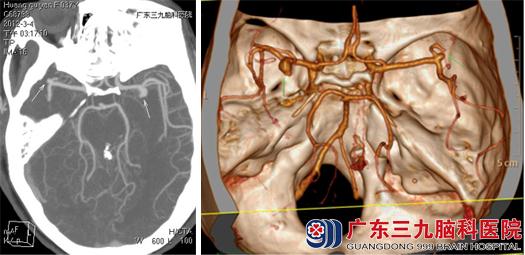

37岁的黄女士因突发头痛、头晕伴呕吐,经朋友介绍来到广东三九脑科医院血管神经外科求医,入院急查CTA提示双侧大脑中分叉处动脉瘤,其中一侧已破裂出血。血管神经外科吾太华主任查看其病情及影像学检查片子后建议尽快接受手术治疗。手术方式有介入栓塞和开颅夹闭两种。由于两个动脉瘤,手术夹闭的风险性很高,术中过度失血、夹闭过程中动脉瘤破裂等几率都比普通的动脉瘤夹闭术要高;介入手术能降低这些风险但却费用较高。患者家属难以承担。黄女士一家在听取了医生对于两种手术的利弊分析后,迫于经济压力决定选择开颅夹闭的治疗方法。

入院第二天,黄女士顺利接受了双侧动脉瘤夹闭术,术中双侧开颅,吾太华主任很顺利地找到了导致黄女士头痛头晕、颅内出血的“元凶”,并在电生理监测下分别夹闭双侧动脉瘤。术程顺利,出血不多,术后予以缓解血管痉挛、止血、补液等治疗。两个星期后,黄女士康复出院。

术前CTA